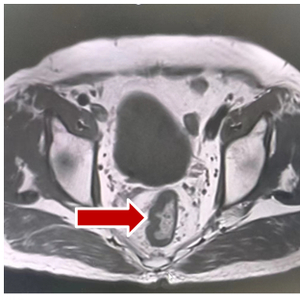

盆腔MRI(2021年04月26日):1.直肠管壁及周围改变,考虑中位直肠癌:T4aN2,CRM(阳性),EMVI(阳性)(图1)。

图1 2021年04月26日盆腔MRI